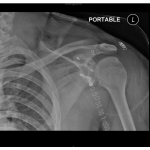

Acromioclavicular Joint Injuries: Myths Debunked

Courtesy: Prof Lennard Funk, Wrightington Upper Limb Unit, Wrightington, UK

AC Joint dislocation: Open Repair

AC Joint dislocation open repair lennard funk from Lennard Funk Courtesy : Prof Lennard Funk, Shoulder Surgeon, Wrightington Upper Limb Unit, United Kingdom